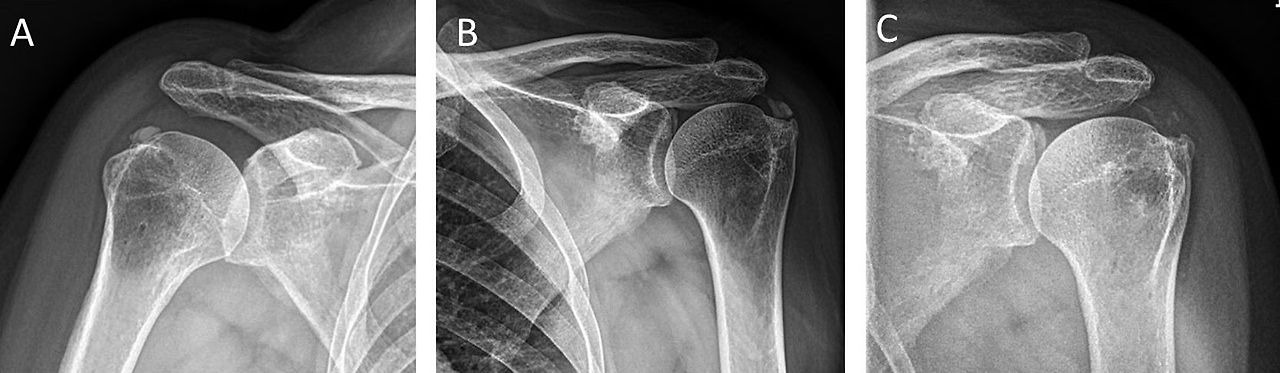

Simple radiographic images of the shoulder anteroposterior view, internal and external rotation views, supraspinatus outlet views, and axillary views should be acquired to determine the location of calcific deposits and predict the possibility of collision symptoms. If follow-up images are acquired, changes in the disease stage can be assessed. In general, the size of the calcific deposits does not change significantly over time, although a previous study reported that 18% of patients experienced an increase in the size of calcific deposits after follow-up for an average of 16 months [12]. According to the classification of Depalma and Kruper [1], radiological findings that show a type 1 pattern, with unclear margins and a fluffy or fleecy appearance, can be judged to be in the resorptive phase in which patients complain of acute pain. On the other hand, if a type 2 pattern with a clear margin and uniform density of calcific deposits is shown, most patients will report little or no pain because they are in the formative or resting phase.

Generally, calcific deposits appear to have a fluffy shape on radiography and a toothpaste-like appearance on arthroscopic findings in the resorptive phase of calcific tendinitis, whereas they appear homogeneously dense on radiography and have a chalk-like appearance on arthroscopic findings in the formative or resting phase of calcific tendinitis (Fig. 1).

Fig. 1.

Radiographic and arthroscopic findings of resorptive and formative or resting phase of calcific tendinitis. (A) In the resorptive phase of calcific deposits (arrows) appear fluffy-like shape on shoulder anteroposterior (AP) view and (B) toothpaste-like appearance on macroscopic findings observed by arthroscopy. (C) In the formative or resting phase of calcific deposits (arrow) appear homogeneously dense on shoulder AP view and (D) chalk-like appearance on macroscopic findings observed by arthroscopy.

석회화 건염의 흡수기 및 형성기 또는 휴지기 단계의 방사선 및 관절경 소견. (A) 흡수기 단계의 석회화 침착물(화살표)은 어깨 정면(AP) 영상에서 푹신한 모양을 보이고, (B) 관절경으로 관찰된 거시적 소견에서는 치약 같은 모양을 보인다. (C) 형성기 또는 휴지기 단계의 석회 침착물(화살표)은 어깨 AP 영상에서 균일하게 고밀도로 나타나며, (D) 관절경으로 관찰된 거시적 소견에서는 분필 같은 모습을 보인다.